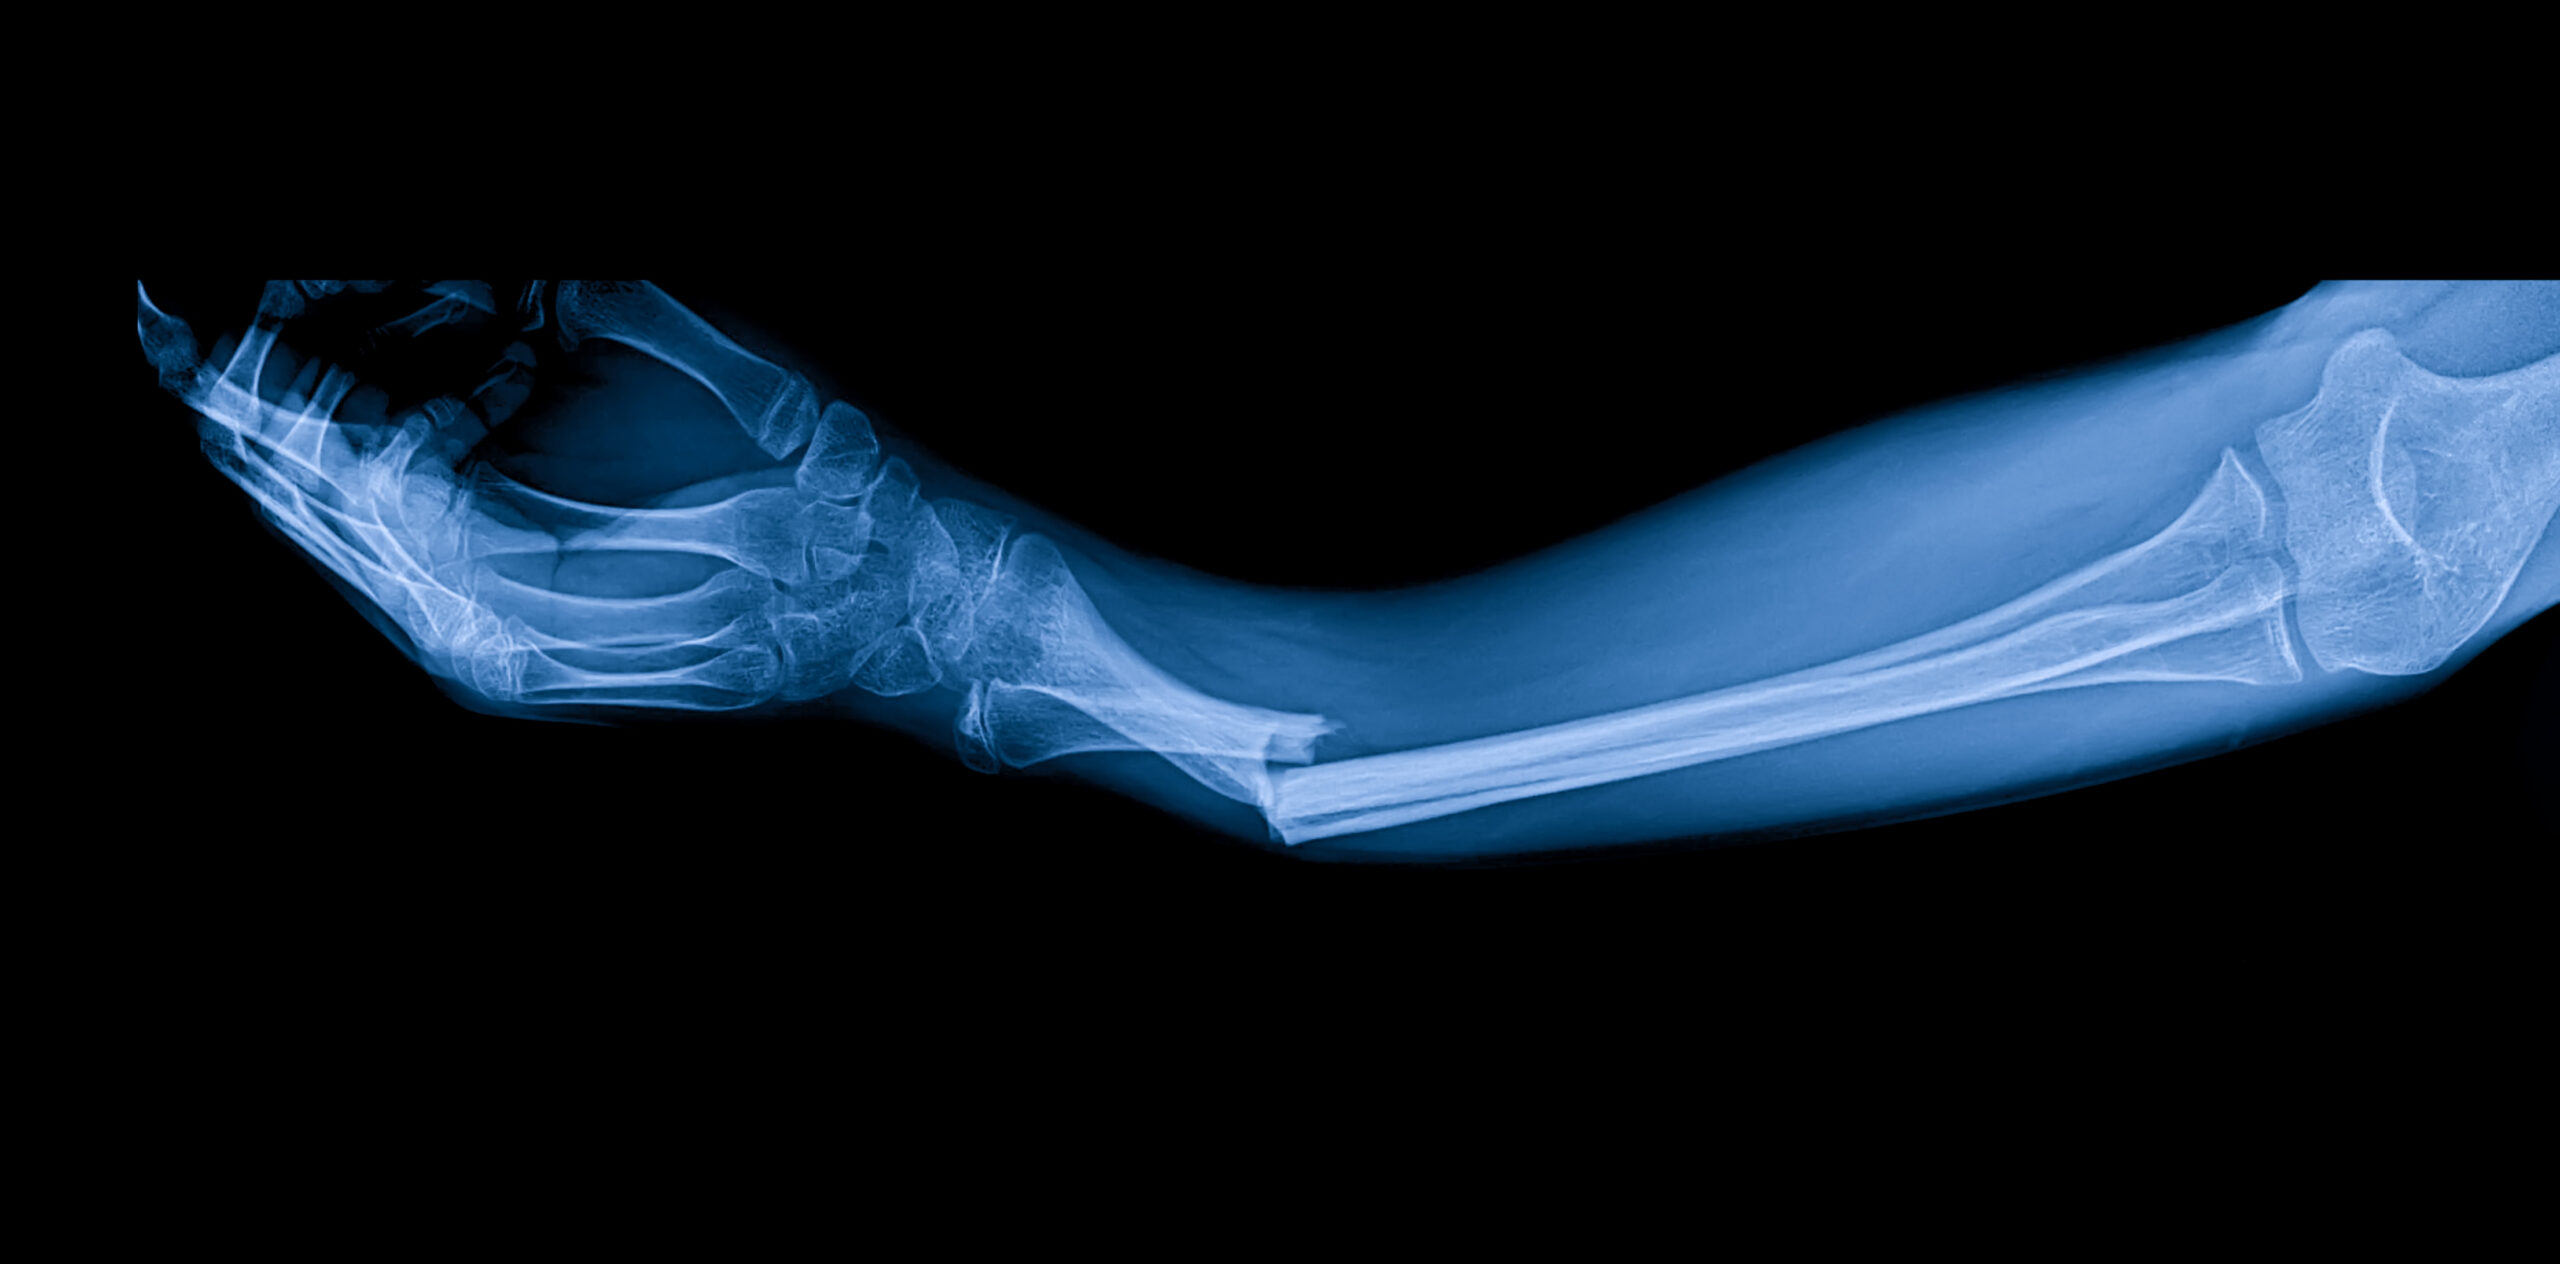

Fracture in Action

Image Source: Anadolu

As a result, a large portion of women enter later adulthood with bones that are already weakened in key weight-bearing areas like the hip and spine. In Caucasian women alone, nearly one in three is affected by osteoporosis, and more than half of bone loss occurs in regions most vulnerable to serious fractures. As bone density declines in these critical areas, even minor falls or low-impact injuries can result in fractures that dramatically alter mobility and quality of life.

These patterns show that fractures are not random events but predictable outcomes of long-term bone weakening. The concentration of bone loss in the hip and spine helps explain why fractures in these areas are both common and severe, often occurring after minor falls rather than major trauma. This reinforces the idea that fracture risk is shaped well before an injury happens, developing gradually as bone density declines over time.